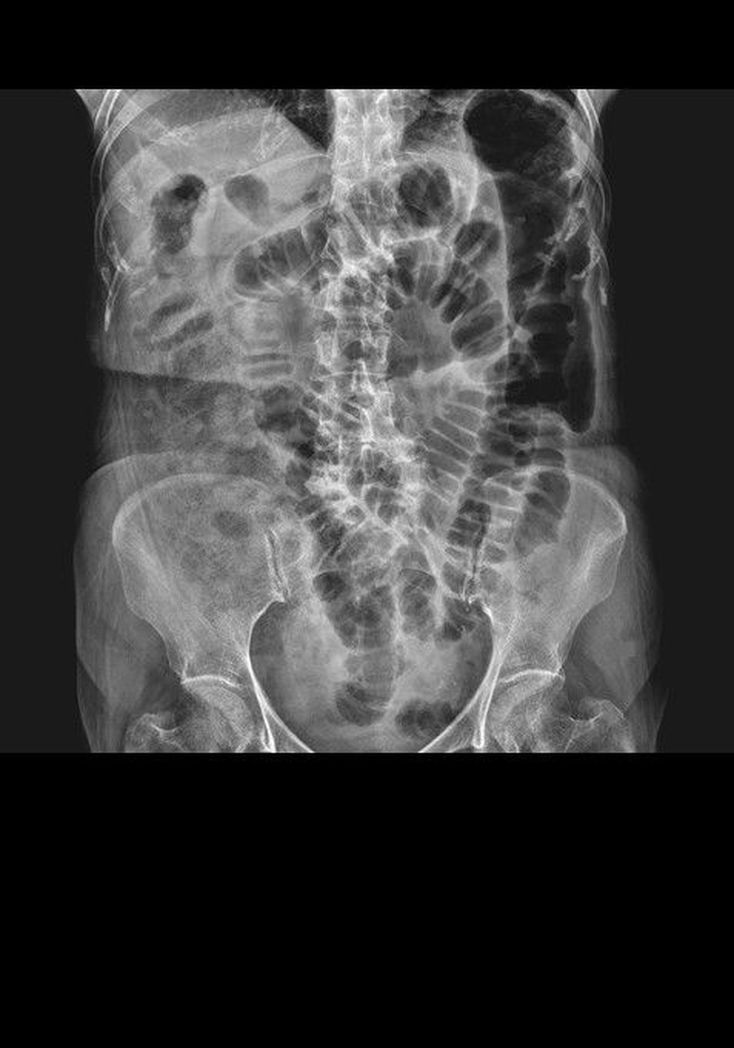

Acute pancreatitis

The colon cutoff sign is classically associated with acute pancreatitis, when inflammation causes spasm or narrowing at the splenic flexure.Note the abrupt termination of gas within the descending colon.